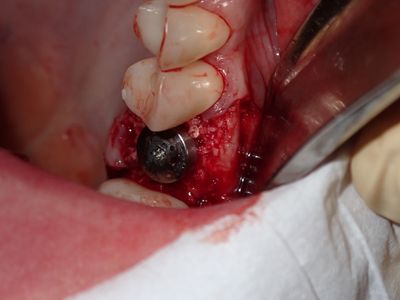

atraumatic exo 26, no loss of labial or palatal plate. Softer bone, implant osteotomy underprepared, difficult/impossible to stretch palatal flap, about 1.5mm exposued at palate, fibrin mmebrance placed on crest, socket grafted with sticky bone from 90/10 mix of mineralized cortical/xenograft